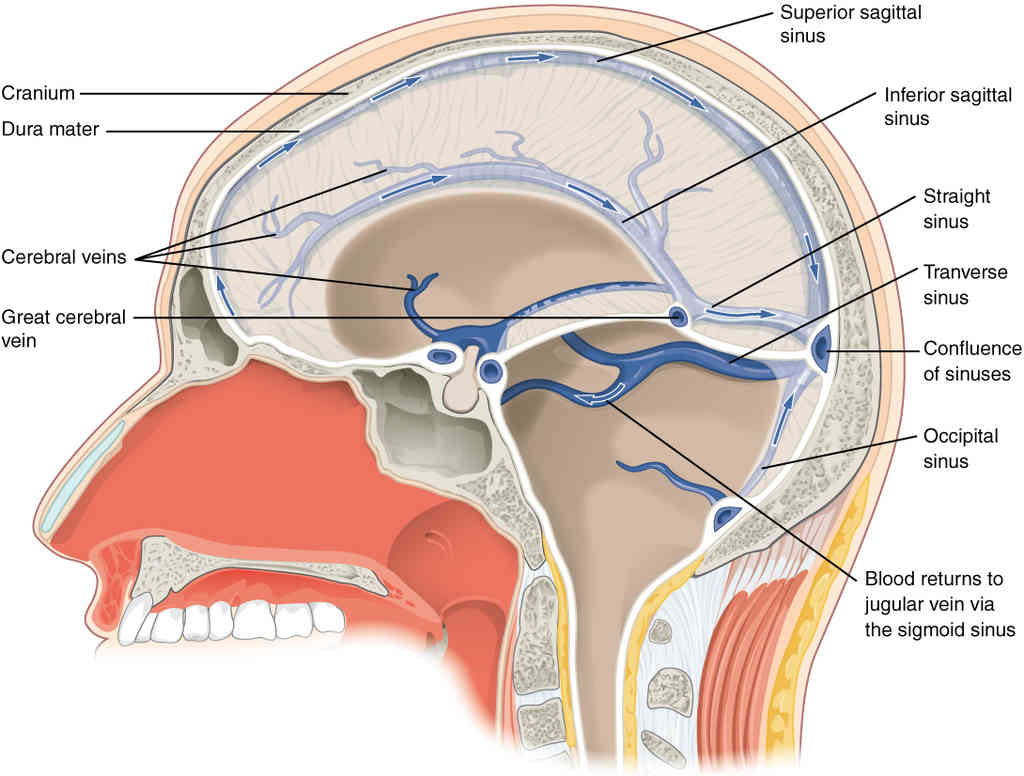

This page is under construction. For now, it is just a resource of the images found in the OpenStax Anatomy and Physiology Handbook. It wil slowly change into a revision tool. Each slide has a number. Use this to refer to the slide. When completed, it will have an unlabelled section, with labelled slides in parallel. On the unlabelled slides, write your answer and use the labelled slide to assess yourself. Keep track by also noting the number on each slide. Improvement at each attempt is important, more so than full marks on a first attempt.